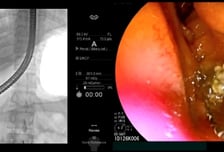

#. 26세 여성 이지은(가명) 씨는 지난달 기름진 음식을 먹고 명치가 심하게 쑤셔 병원 응급실을 찾았다. 복부CT(컴퓨터단층촬영) 등 검사를 받았지만 별다른 이상은 발견되지 않았고, 몇 시간 뒤 통증이 가라앉자 집으로 돌아갔다. 그러나 다음날 통증이 더 심해졌고 열과 함께 눈이 노랗게 변해 다시 응급실로 왔다. 담석증이 의심돼 초음파내시경 검사를 받은 결과, '담관결석(담석의 일종)'으로 진단받았다. 담석은 담즙이 뭉쳐져 돌처럼 단단하게 응고된 덩어리다. 담즙 성분의 비율이 변하면서 담석이 생기는 것으로 알려졌다. 담석은 주로 담즙을 보관하는 주머니(담낭)에서 생겨난 뒤, 담즙이 흐르는 담낭관·총담관으로 이동해 문제를 일으킨다. 총담관은 간내 담관·담낭에서 나오는 담낭관이 합류하는 관으로, 십이지장까지 연결된다. 담석이 있다고 무조건 증상이 나타나는 건 아니다. 담석을 가진 환자의 80%는 특별한 문제 없이 생활한다. 하지만 20%는 담석이 담낭관이나 총담관을 막아 통증을 유발하거